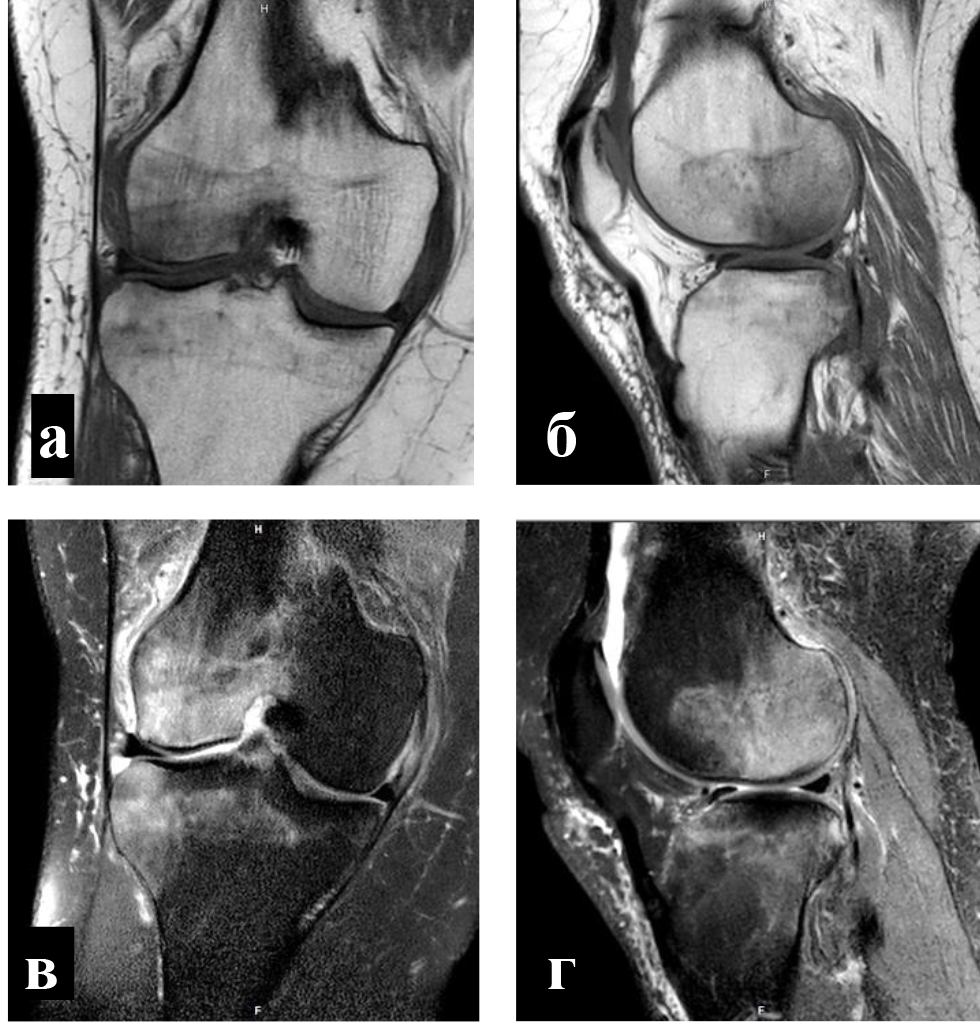

Критериями включения в научное исследование являлись: первичный ОА коленного сустава II или III стадии по классификации K-L, наличие зон трабекулярного отека костного мозга в области мыщелков бедренной или (и) большеберцовой костей по данным МРТ, интенсивность болевого синдрома не менее 6 баллов по визуальной аналоговой шкале (ВАШ), недостаточная эффективность проведенного ранее консервативного лечения.

Для определения локализации и распространенности перегрузочного отека костного мозга всем пациентам выполняли МРТ. На Т1-взвешенных изображениях визуализировали снижение интенсивности сигнала, на Т2-взвешенных изображениях с жироподавлением и на коротких последовательностях «восстановления – инверсии» (STIR) выявляли высокую интенсивность сигнала (рис. 1).

Объективным показателем регресса болевого синдрома и нормализации клеточного метаболизма субхондральных структур являлось значительное сокращение объема или вовсе исчезновение зон трабекулярного отека костного мозга, что подтверждалось уменьшением гиперинтенсивных участков по данным МРТ (рис. 4) [8].